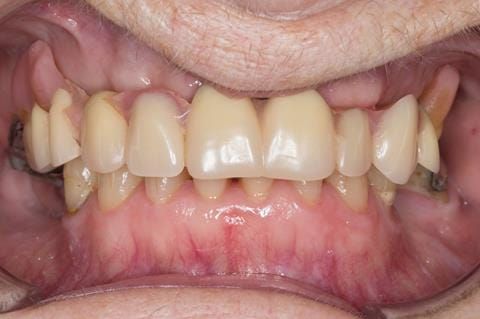

- Poorly fitting cobalt chromium based maxillary partial denture, which has been added to. This exhibited poor retention, stability and tissue fit (support). Unable to wear a new acrylic based denture.

- Eight mandibular anterior teeth worn incisal edges from now extracted maxillary anterior crowns. Gingivitis - owing to inadequate oral hygiene.

Following consultation and second discussion appointment the patient chose to have option 2 namely, a window denture - maxillary cobalt chromium based partial denture. The clinical situation and treatment process is shown in detail below with photographs. The patient was successfully rehabilitated with this and her quality of life considerably improved. The clinical work was provided by Finlay and the technical work by Rowan.